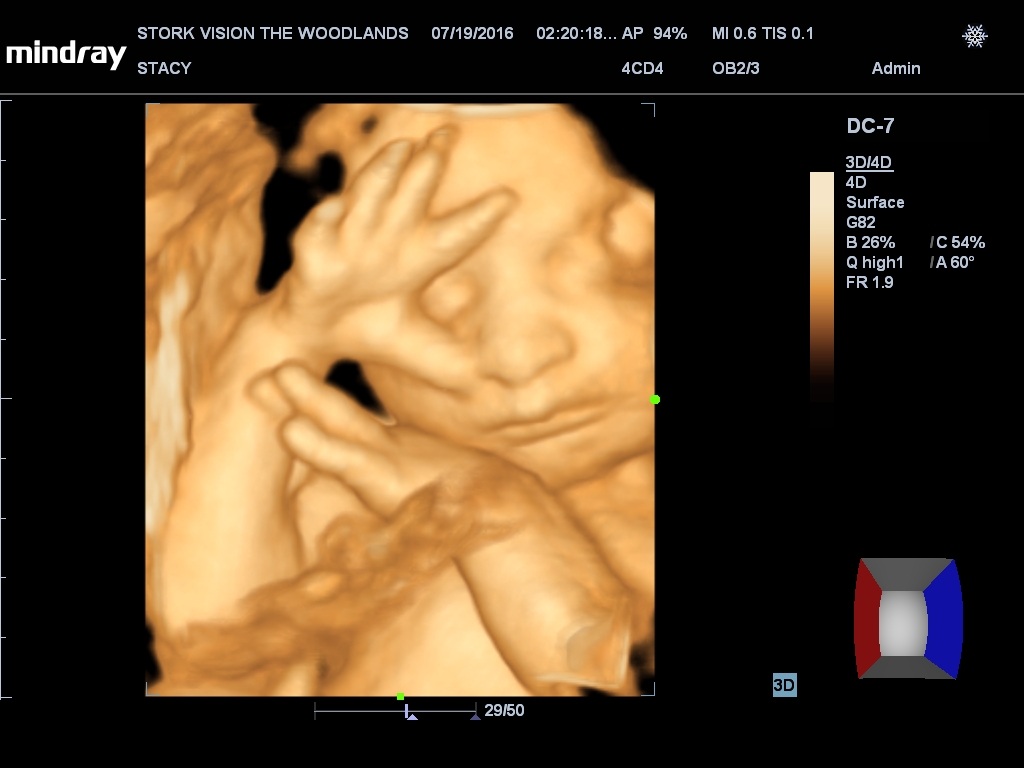

Best moment the week: Seeing Juliette on the 3D/4D ultrasound. So amazing!